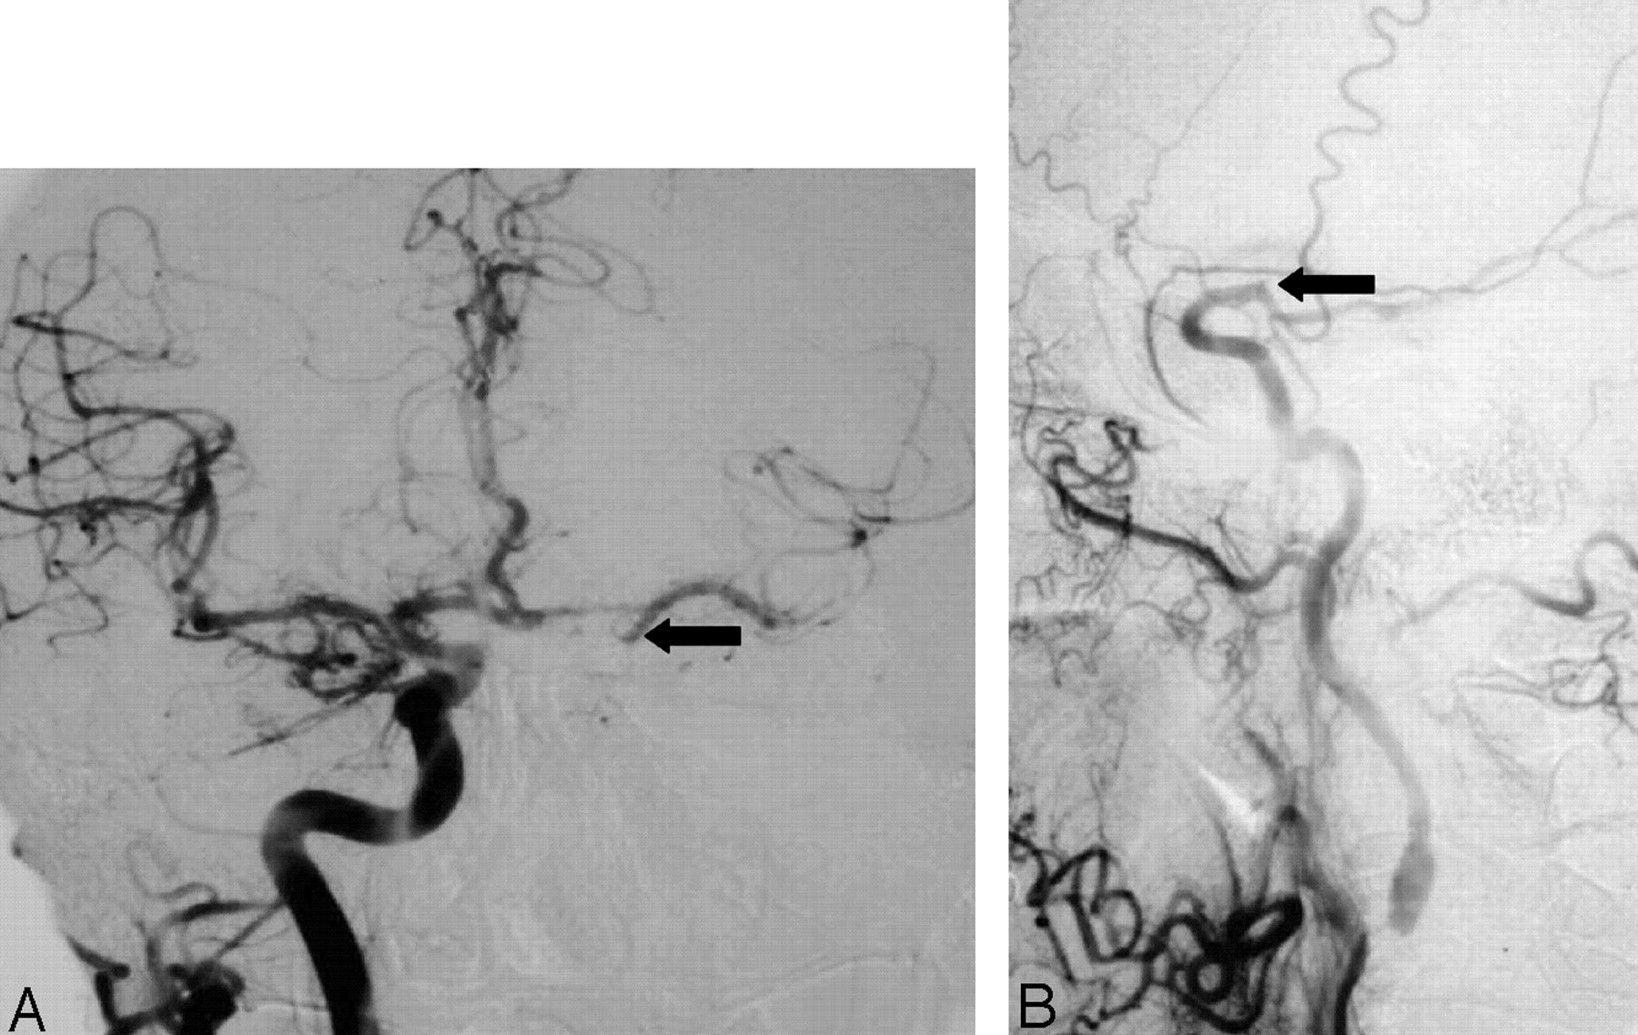

Collaterals (cross-filling and dilution) and late arrival of ICA to the head.

A, Anterioposterior right carotid angiogram, head view, contralateral to left near occlusion shows exuberant cross-filling to left middle cerebral branches and even slightly down the supraclinoid carotid (arrow) to supply the anterior choroidal artery.

B, Lateral left carotid angiogram, late arterial neck and head view, shows delay in ICA filling intracranially, and abrupt dilution contrast in the supraclinoid carotid (arrow) above the origin of a fetal-type posterior cerebral artery. This dilution indirectly demonstrates the excellent collateral already shown in A, not opacified here. It also shows the supraclinoid carotid site of the “watershed” between the right carotid source and the extremely severe left carotid stenosis.